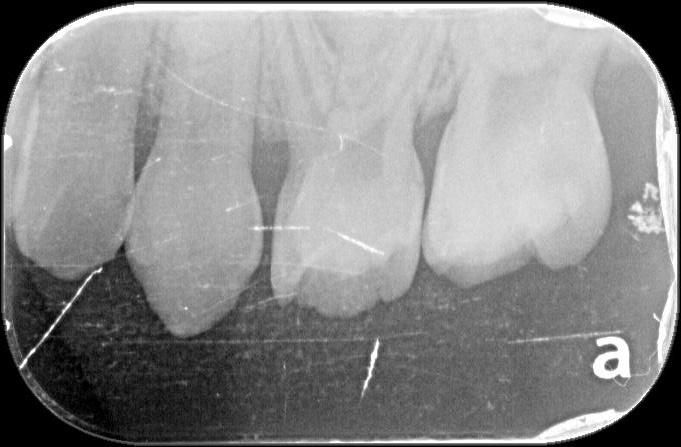

4살아이 눈으로도 시급한게 아래2개 위에 2개정도입니다.그런데 10개나 치료해야되고 8개를 크라운을 씌워야 된다고 하는데요 사진상에도 그런가요?

x-ray 사진상에서 치아와 치아 사이 충치가 있습니다. 어금니 치아와 치아 사이 충치는 눈에 잘 안보이지만 안으로 많이 진행된 경우가 많습니다.

사진에서는 올려주신 치아 대부분에 충치가 보입니다. 정확한 갯수는 알 수 없으나 다수 치료해야합니다.

2. 사진상에서 보이는 치아들은 충치가 있는게 다수이며 첫번째 사진의 오른쪽 치아, 세번째 사진의 왼쪽 치아는 충치가 심해보입니다.